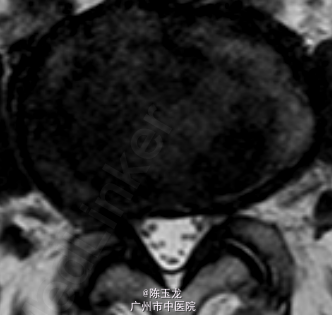

体查:腰椎活动稍受限,腰部有明显叩击痛,左小腿外侧区域感觉减退;双侧直腿抬高试验(—)。 辅助检查:三大常规、血生化、肝肾功能未见明显异常。腰椎MRI示:L4/5椎间盘突出。图片如下。